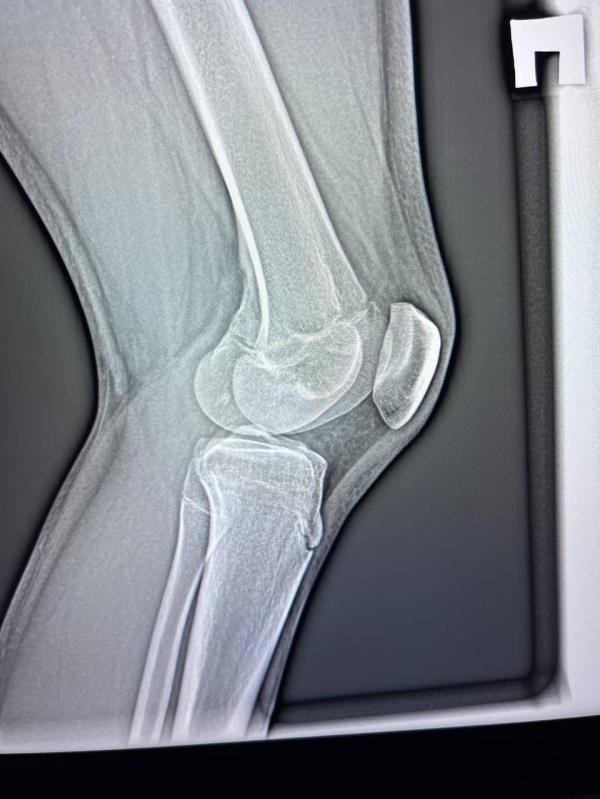

Артрит у подростка 14 лет: что видно на рентгене в 2-х проекциях?

post image 2

Неделю назад поставили артрит в 2-х проекциях, сегодня сделали рентген, кто-то разбирается ? Здесь что-то видно ?

Подросток 14 лет…